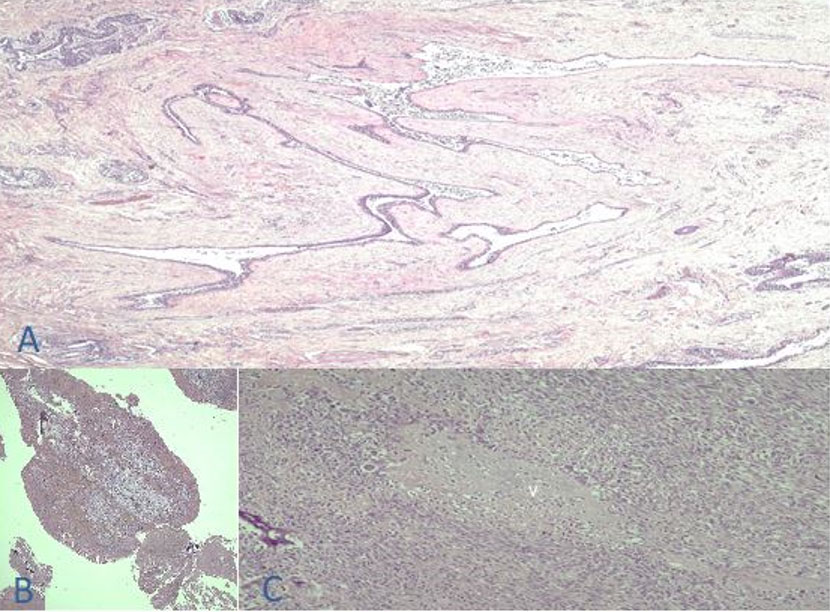

On the 19th day post-resection, the patient underwent reconstruction via split thickness skin grafting. Graft site was opened on the 5th day post-reconstruction with note of good uptake around 90%, and the patient was subsequently sent home after few days. Final histopathology of the patient revealed malignant phyllodes tumor, left stage IIIB (T4N0M0 G3) with all margins negative for tumor (Figure 7, Figure 8, Figure 9). Tumor size is 30 cm in widest dimension and on microscopy, there is noted marked stromal cellularity and stromal atypia. Stromal overgrowth is as well present and mitotic rate was 24–26 per 10 high-power field (hpf).

Figure 9: Histopathology report. Breast, Left—Phyllodes tumor, malignant. (A) Leaf-like patterns of the ducts induced by stromal overgrowth. (B) Fibromyxoid stroma with chronic inflammation and hemorrhage. (C) Cartilaginous differentiation from malignant stromal elements (Chondrosarcomatous elements). Tumor size 30 cm in widest dimension. Skin and nipple: Negative for tumor involvement. Stromal cellularity: Marked. Stromal atypia: Marked. Stromal overgrowth: Present. Mitotic rate: 24–26/10 hpf. Histologic tumor border: Infiltrative. All margins negative for tumor (Basal 6 cm, Superior: 5 cm, Inferior: 2 cm, Medial: 3 cm, Lateral: 4 cm).